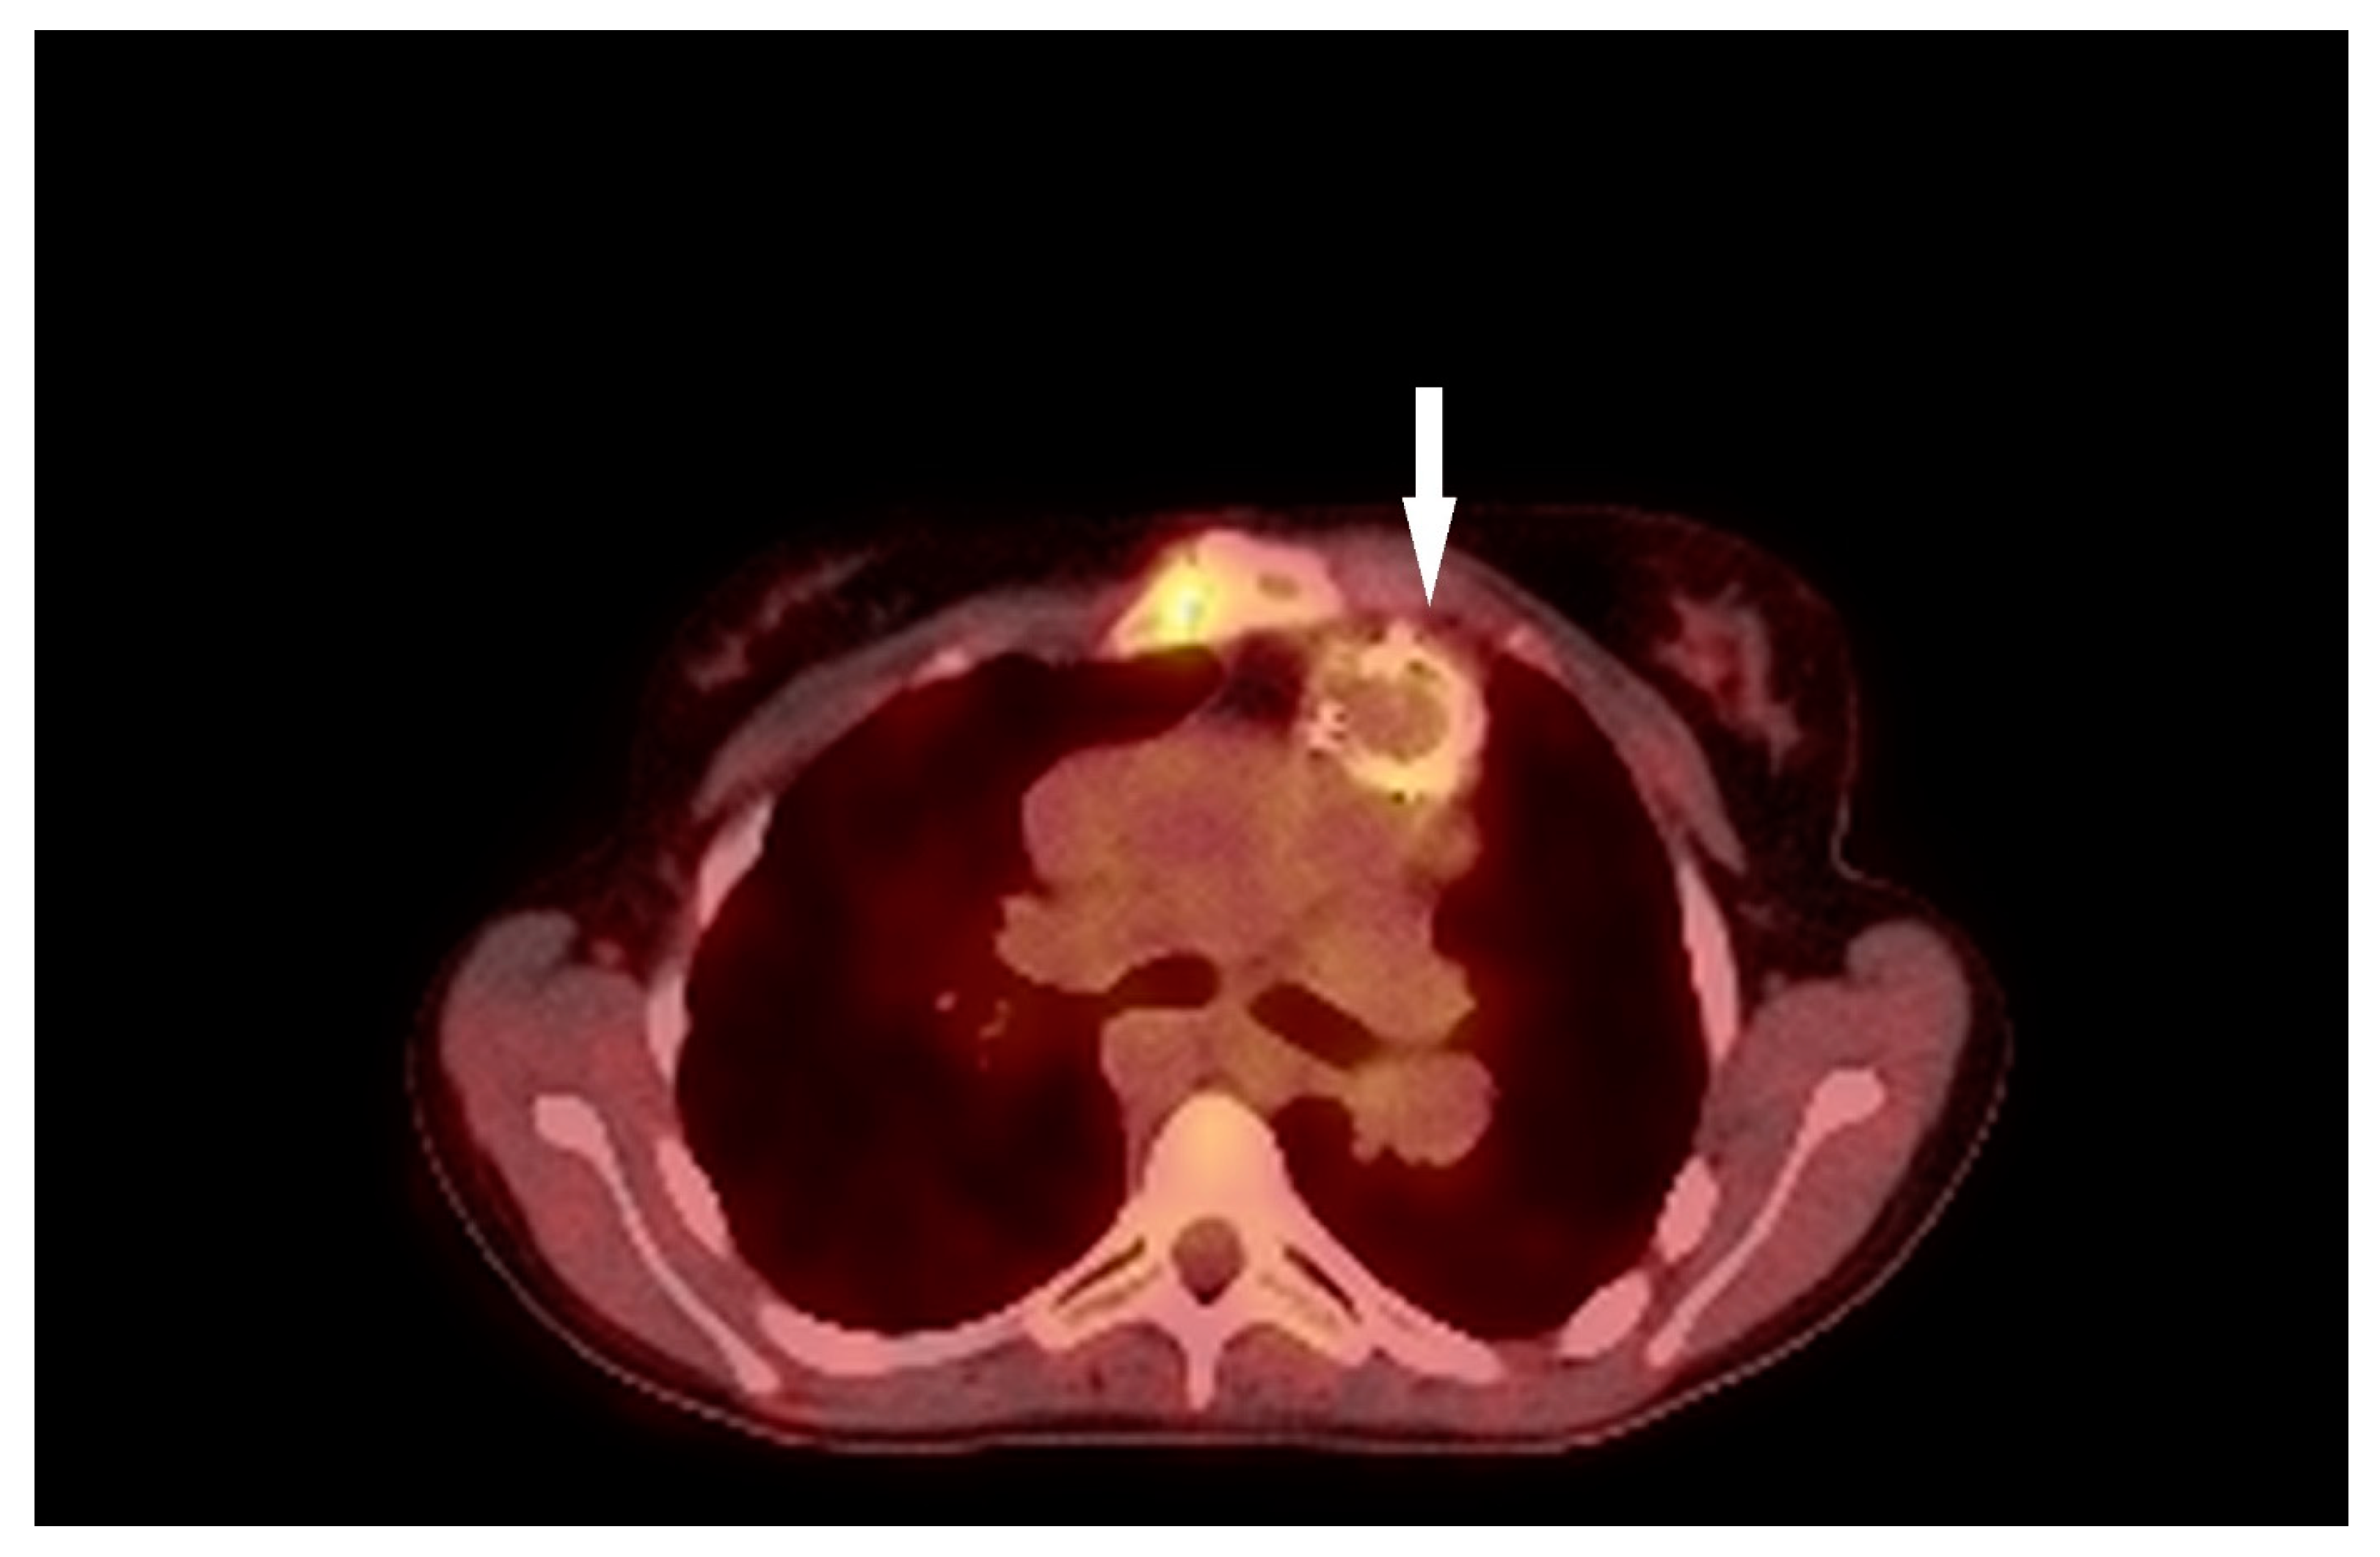

3.3. Case 3